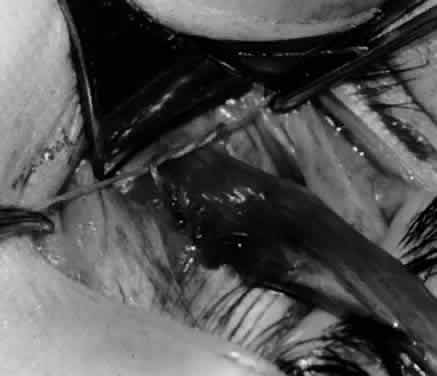

Fig. 24. The eyelid speculum is removed and a Desmarres lid retractor is placed inferiorly. The inferior oblique muscle is drawn superiorly and nasally. The fusiform expansion of the inferior oblique muscle is evident on the posterior border, where the nerve to the inferior oblique muscle and artery and vein enter the inferior oblique muscle. The Stevens muscle hook is used to hook the neurovascular bundle.

Fig. 25. The hook is advanced further for identification of the neurovascular bundle on the inferior oblique muscle.

Fig. 26. Cautery is applied to sever the neurovascular bundle, and a sponge is used to protect the sclera and lids from cautery.

Fig. 27. As the neurovascular bundle is severed completely, the inferior oblique muscle will be released of the normal tension provided by the neurovascular bundle on the posterior border of the inferior oblique muscle.